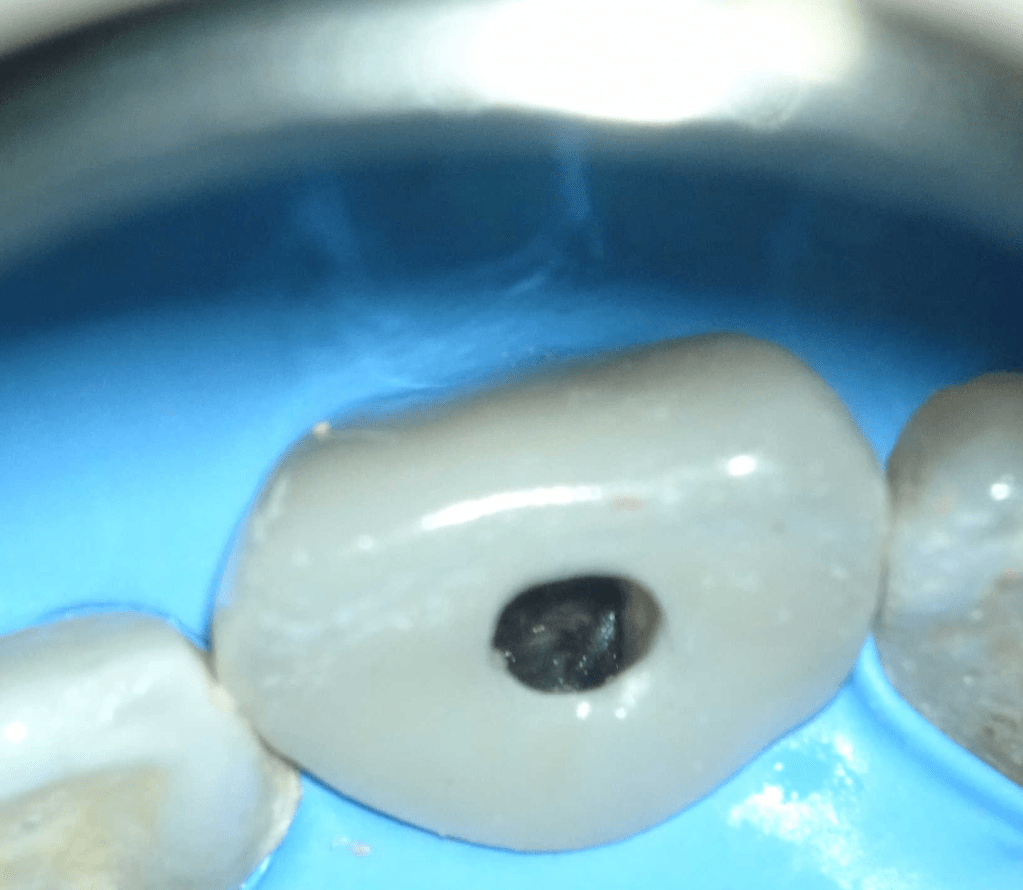

Pulpotomía biodentine + reco preendio